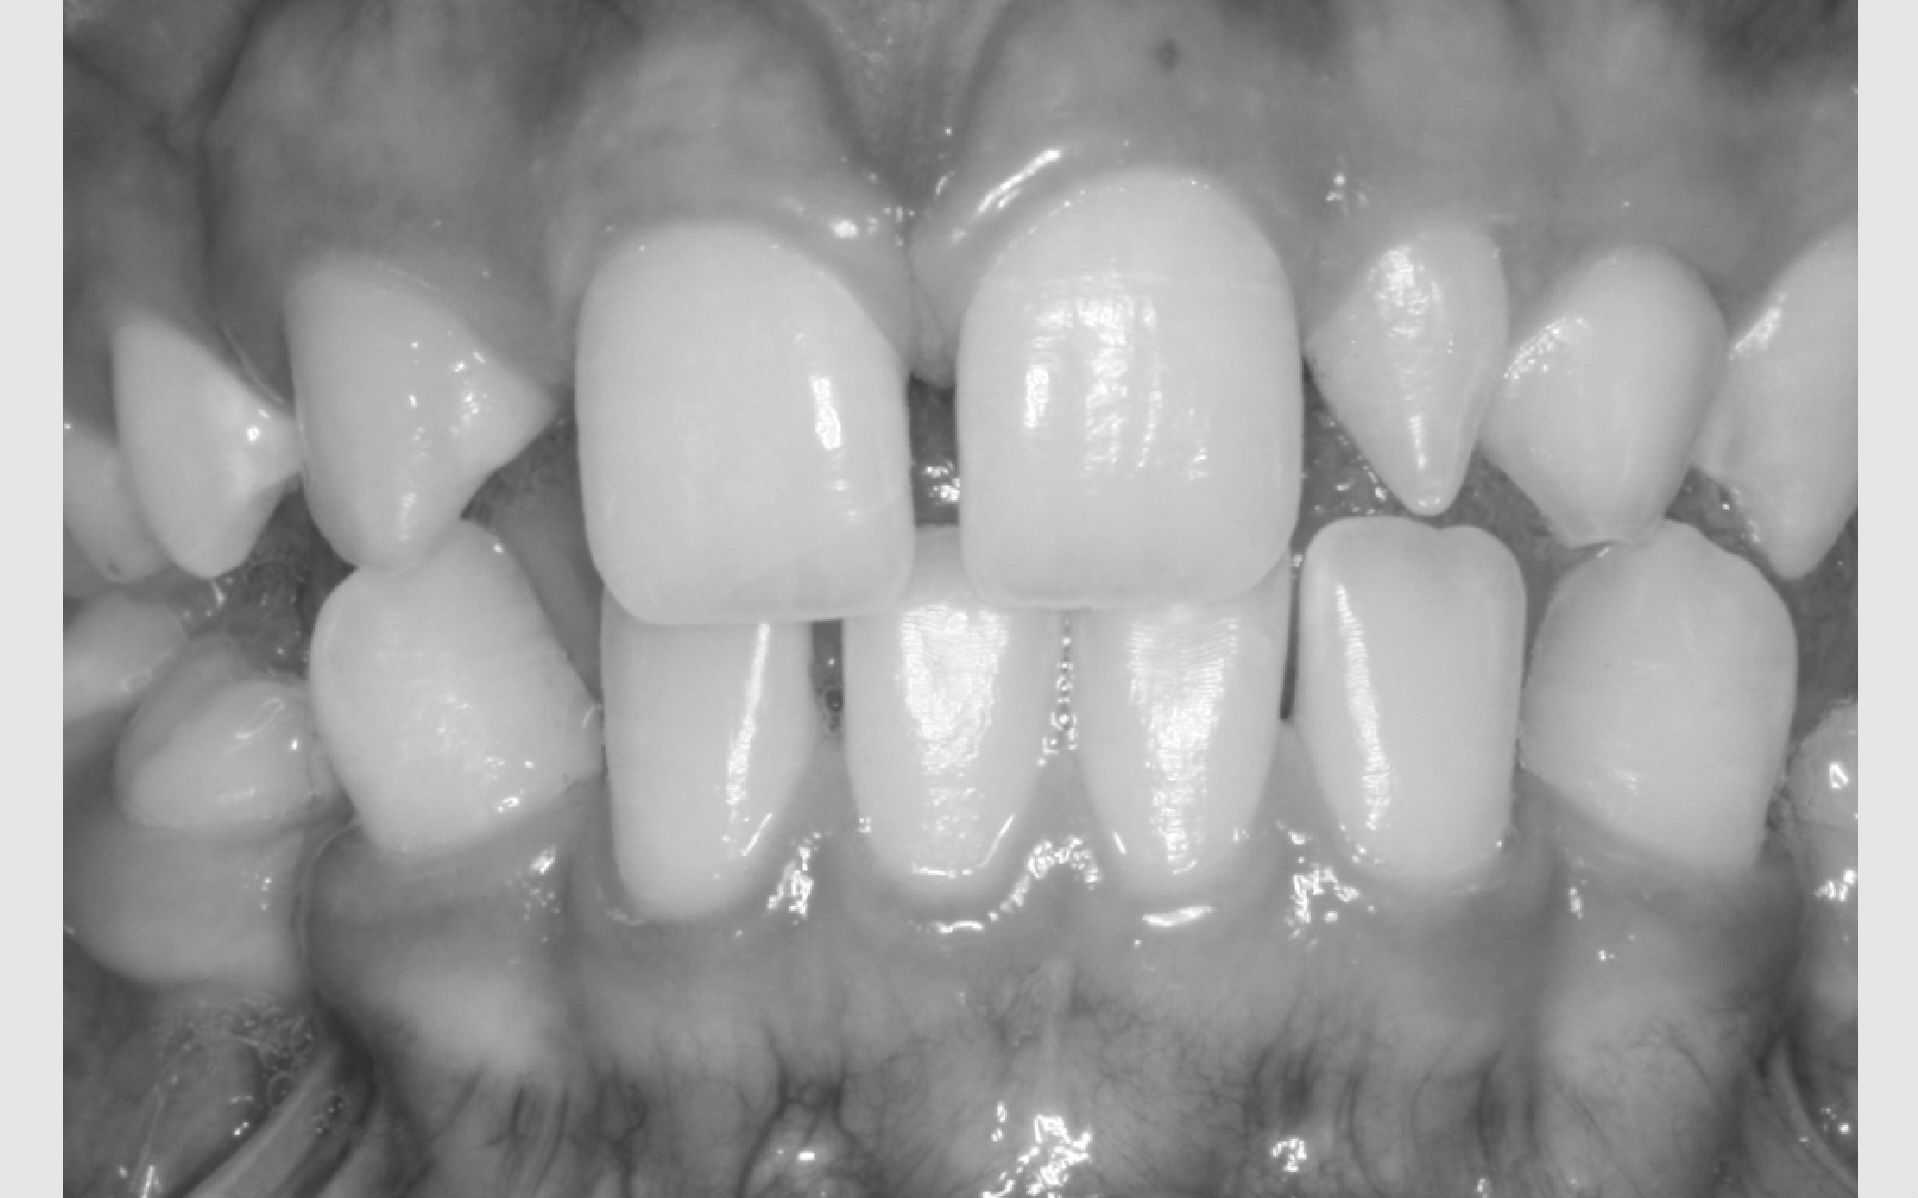

Studiemateriale, består af modeller, fotos og røntgenbilleder af tænder og ansigt. Der bliver også udleveret et helbredsskema, som skal udfyldes på stedet. Det er vigtigt at vide, om jeres barn er sundt og raskt, eller om der er særlige hensyn, vi skal tage - eksempelvis til medicin med videre.

Der bliver taget billeder "udenpå og indeni" samt røntgenbilleder.

Dit barn skal selv holde sine læber til side med en læbeholder, mens tænderne bliver fotograferet. Billederne har følgende formål: